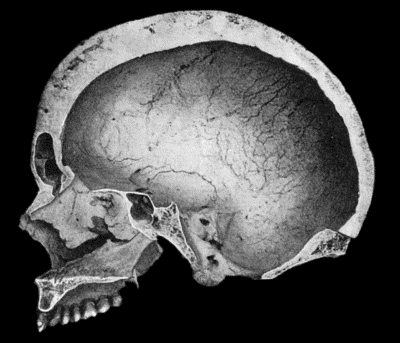

130.Syphilitic Disease of Skull 463

134.Changes in the Skull resulting from Ostitis Deformans 474

General Treatment.—The patient should be kept at rest, preferably in bed, to diminish the general tissue waste; and the diet should be restricted to fluids, such as milk, beef-tea, meat juices or gruel, and these may be rendered more easily assimilable by artificial digestion if necessary. To counteract the general effect of toxins absorbed into the circulation, specific antitoxic sera are employed in certain forms of infection, such as diphtheria, streptococcal septicæmia, and tetanus. In other forms of infection, vaccines are employed to increase the opsonic power of the blood. When such means are not available, the circulating toxins may to some extent be diluted by giving plenty of bland fluids by the mouth or normal salt solution by the rectum.

Before applying leeches the part must be thoroughly cleansed, and if the leech is slow to bite, may be smeared with cream. The leech is retained in position under an inverted wine-glass or wide test-tube till it takes hold. After it has sucked its fill it usually drops off, having withdrawn a dram or a dram and a half of blood. If it be desirable to withdraw more blood, hot fomentations should be applied to the bite. As it is sometimes necessary to employ considerable pressure to stop the bleeding, leeches should, if possible, be applied over a bone which will furnish the necessary resistance. The use of styptics may be called for.